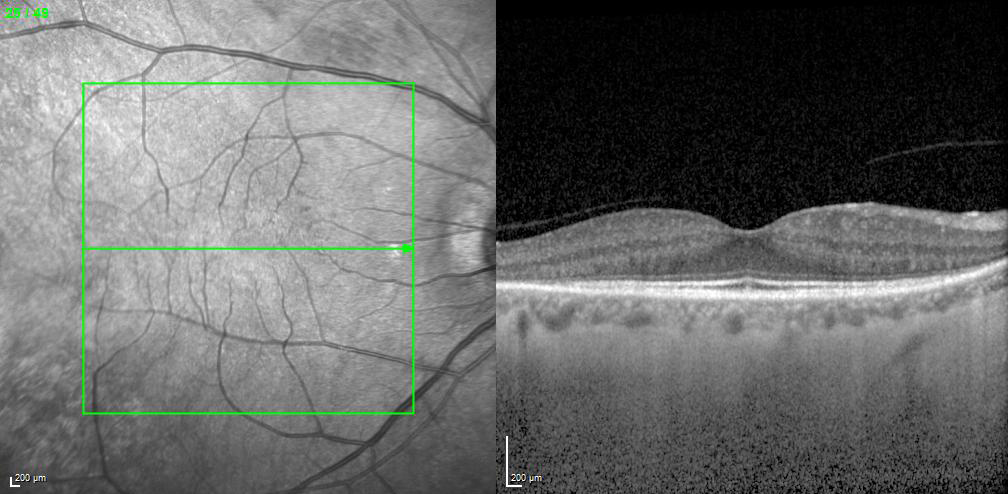

EDI – Enhanced Depth Imaging Mode

The Enhanced Depth Imaging Mode (EDI) of the SPECTRALIS is an OCT imaging technology that enables better visualization of choroidal vasculature. By automatically inverting the image and leveraging the benefits of technologies like TruTrack Active Eye Tracking and Noise Reduction, SPECTRALIS delivers superior images to depict the choroid, allowing to manually measure choroidal thickness.

Retinal and choroidal thickness in pediatric patients with sickle cell disease: a cross-sectional cohort study

An Evaluation of Choroidal and Retinal Nerve Fiber Layer Thicknesses Using SD-OCT in Children with Childhood IgA Vasculitis